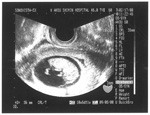

病院の先生に赤ペンで落書きされてしまったエコーです。

水性の赤ペンだったのか、エコーがうっすら見えている状態でしたので修復可能でした。

黒マジックだったらまず無理だったと思います。

もし黒マジックだったとしたら。。。周辺の状況から予測で書き込み修復も出来るのですが、本当の状態ではないため気がひけます。

エコーの状況はそれぞれで、お電話では状況判断をしにくいので、お店の方へ持って来て頂くか、遠方の方でしたら一度送って頂く必要があります。

(申し訳ありませんが往復の送料はお客様負担になります) |